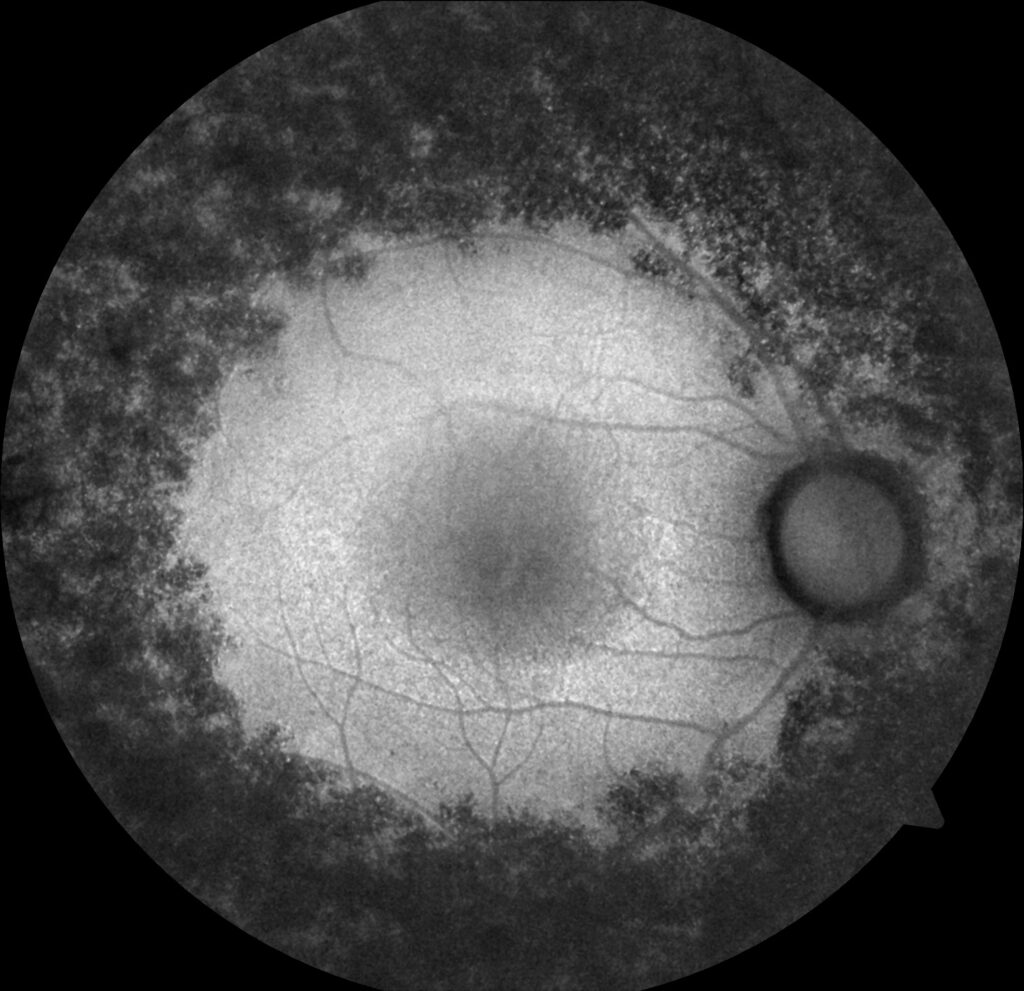

A 26-year-old female patient with cystoid macular edema (CME) secondary to retinitis pigmentosa (RP). Pretreatment OCTs show CME bilaterally. After one month of topical Brinzolamide treatment, visual acuity improved from 20/50 to 20/30 and CME resolved bilaterally.